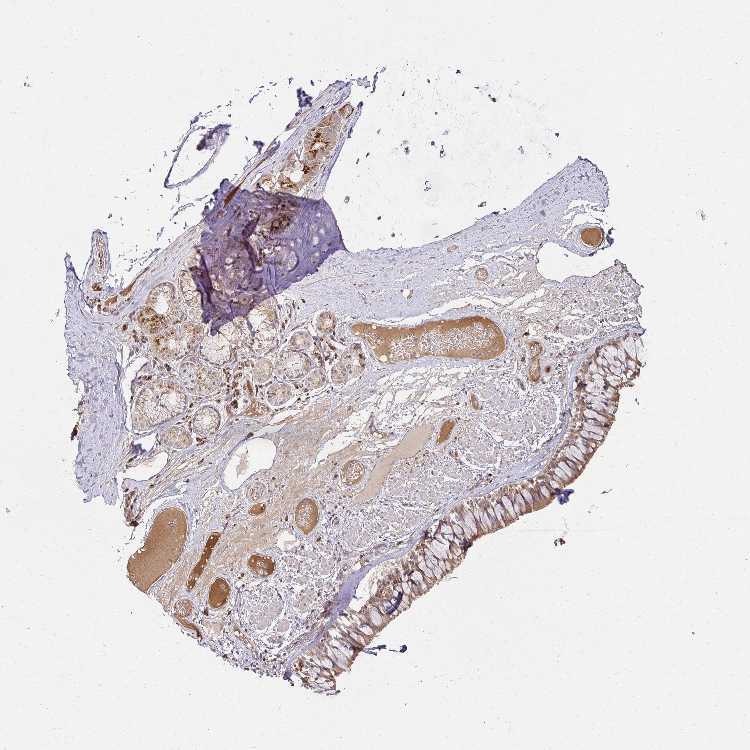

SOFT TISSUE 1 - Antibody stainingi

Antibody staining in the annotated cell types in the current human tissue is reported as not detected, low, medium, or high, based on conventional immunohistochemistry profiling in selected tissues. This score is based on the combination of the staining intensity and fraction of stained cells.

Each image is clickable and will lead to virtual microscopy that enables deeper exploration of all samples and also displays staining intensity scores, fraction scores and subcellular localization as well as patient and tissue information for each sample.

Antibody HPA046979Antibody HPA054254Antibody CAB025901

Chondrocytes LowNot detected-

Fibroblasts LowLowMedium

Peripheral nerve --Not detected